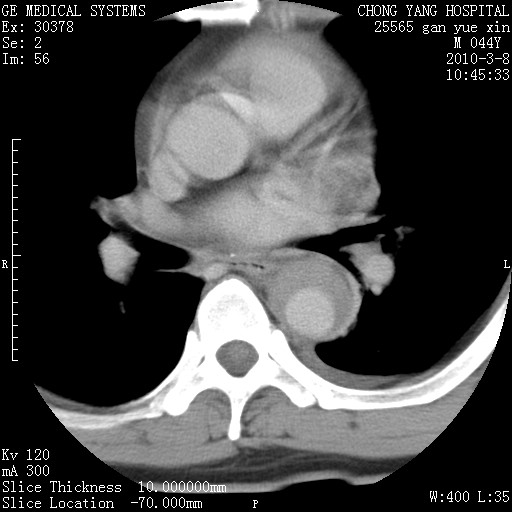

标题: CT24940:主动脉增强,典型病例。 [打印本页]

标题: CT24940:主动脉增强,典型病例。

夹层动脉瘤。

动脉夹层

夹层动脉瘤,典型

主动脉夹层。

动脉夹层的分型:

⒈debakey分型:根据主动脉夹层累及部位,分为三型:ⅰ型:原发破口位于升主动脉或主动脉弓部,夹层累及升主动脉、主动脉弓部、胸主动脉、腹主动脉大部或全部,少数可累及髂动脉。ⅱ型:原发破口位于升主动脉,夹层累及升主动脉,少数可累及部分主动脉弓。ⅲ型:原发破口位于左锁骨下动脉开口远端,根据夹层累及范围又分为ⅲa,ⅲb。ⅲa型:夹层累及胸主动脉。ⅲb型:夹层累及升主动脉、腹主动脉大部或全部。少数可累及髂动脉。

⒉stanford分型:a型:夹层累及升主动脉,无论远端范围如何。b型:夹层累及左锁骨下动脉开口以远的降主动脉。

夹层动脉瘤,少量胸水

夹层动脉瘤;左侧少量胸腔积液。

典型主动脉夹层。